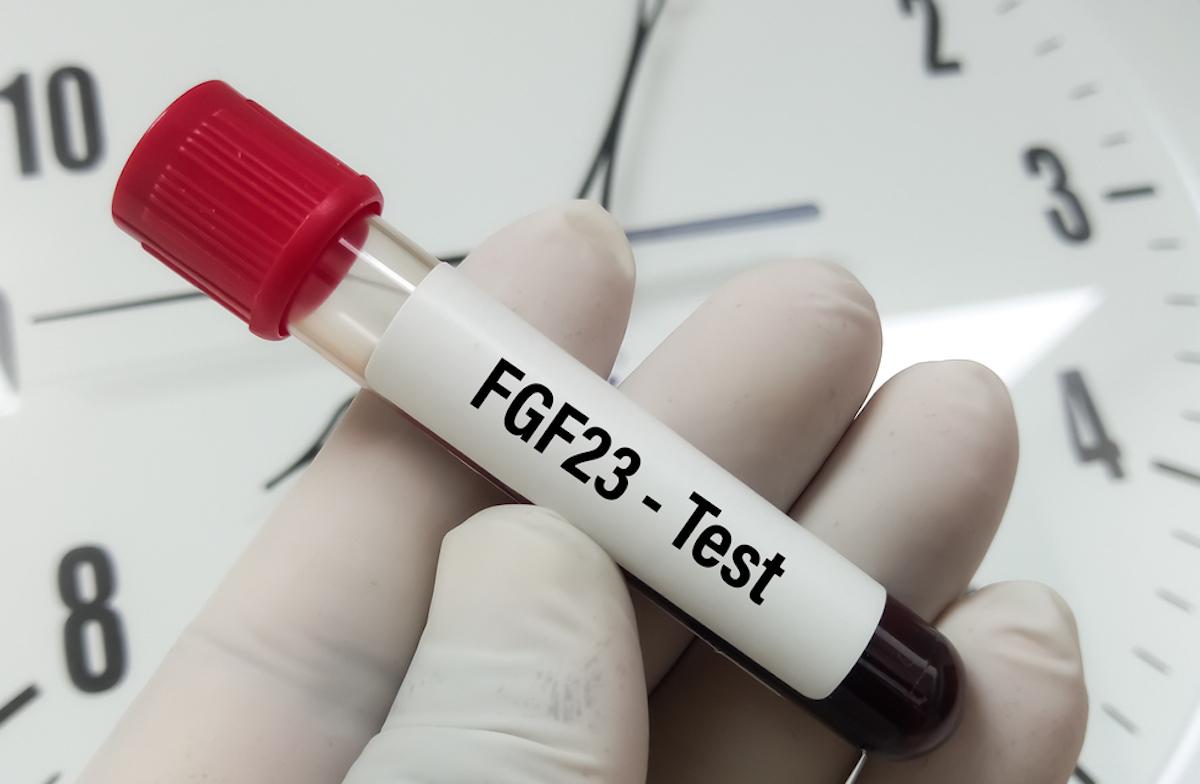

L’ostéomalacie induite par des tumeurs, dite « tumor-induced osteomalacia », est historiquement la forme acquise la plus fréquente d’hypophosphatémie liée au facteur de croissance fibroblastique 23 (FGF23). L’excès de FGF23 sécrété par la tumeur provoque une fuite rénale de phosphate, menant à des fragilités osseuses et à des douleurs osseuses diffuses. Le traitement de première intention consiste en l’ablation chirurgicale de la tumeur en cause. Toutefois, chez 27 à 45 % des patients suspects de cette pathologie, aucun foyer tumoral n’est décelable malgré des investigations exhaustives.

Cette constatation a soulevé l’hypothèse qu’une autre étiologie, possiblement auto-immune, puisse être à l’origine de ces hypophosphatémies liées au facteur de croissance fibroblastique 23 (FGF23) dites « inexpliquées ». Des chercheurs ont émis l’hypothèse que des autoanticorps dirigés contre les protéines régulant la phosphatémie pourraient expliquer ces formes « tumor-like ».

Dans une étude japonaise, des échantillons de sérum prélevés sur des patients et des témoins ont été soumis à une recherche d'auto-anticorps dirigés contre les protéines responsables de la FGF23rHR congénitale, notamment DMP1, ENPP1, FGFR1 et PHEX (phosphate-regulating endopeptidase X-linked). Ils ont tidentifié 13 patients avec des caractéristiques d’ostéomalacie liée à un excès de FGF23, mais sans tumeur détectable, après un criblage génétique et tumoral approfondi.

L’analyse sérologique a mis en évidence, chez 4 patients, des autoanticorps dirigés contre la protéine PHEX (Phosphate-regulating endopeptidase homolog, X-linked) à l’aide d’un immunodosage LIPS (luciferase immunoprecipitation system). Un second test par cytométrie en flux a confirmé cette séropositivité et a permis d’en identifier un cinquième, totalisant 5 patients (38 %) avec autoanticorps anti-PHEX. Ainsi, une ostéomalacie ressemblant à la forme tumorale, mais sans foyer détectable, pourrait relever d’un nouveau mécanisme auto-immun.

Les données présentées proviennent d’un processus de sélection rigoureux : tous les patients avaient un tableau clinique d’hypophosphatémie persistante et de fractures ou douleurs osseuses compatibles avec un excès de FGF23. Après exclusion des causes génétiques et tumorales (imagerie, examens biologiques, analyses génétiques ciblées), une analyse sérologique par immunoessai (LIPS) a été conduite pour rechercher la présence d’autoanticorps dirigés contre des protéines déjà incriminées dans les formes congénitales d’hypophosphatémie (DMP1, ENPP1, FGFR1 et PHEX). L’approche a été renforcée par cytométrie en flux, permettant de détecter d’éventuelles conformations antigéniques non décelées par la technique initiale.